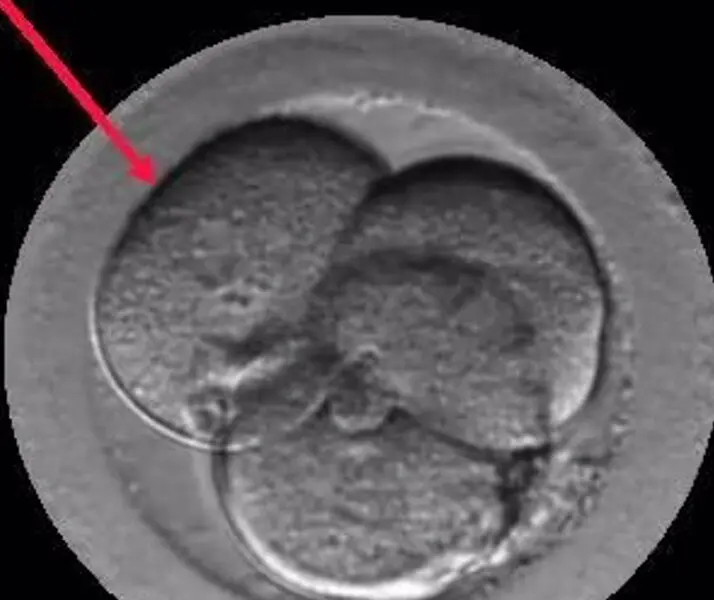

Embrión Multinucleado. - Institut Marquès